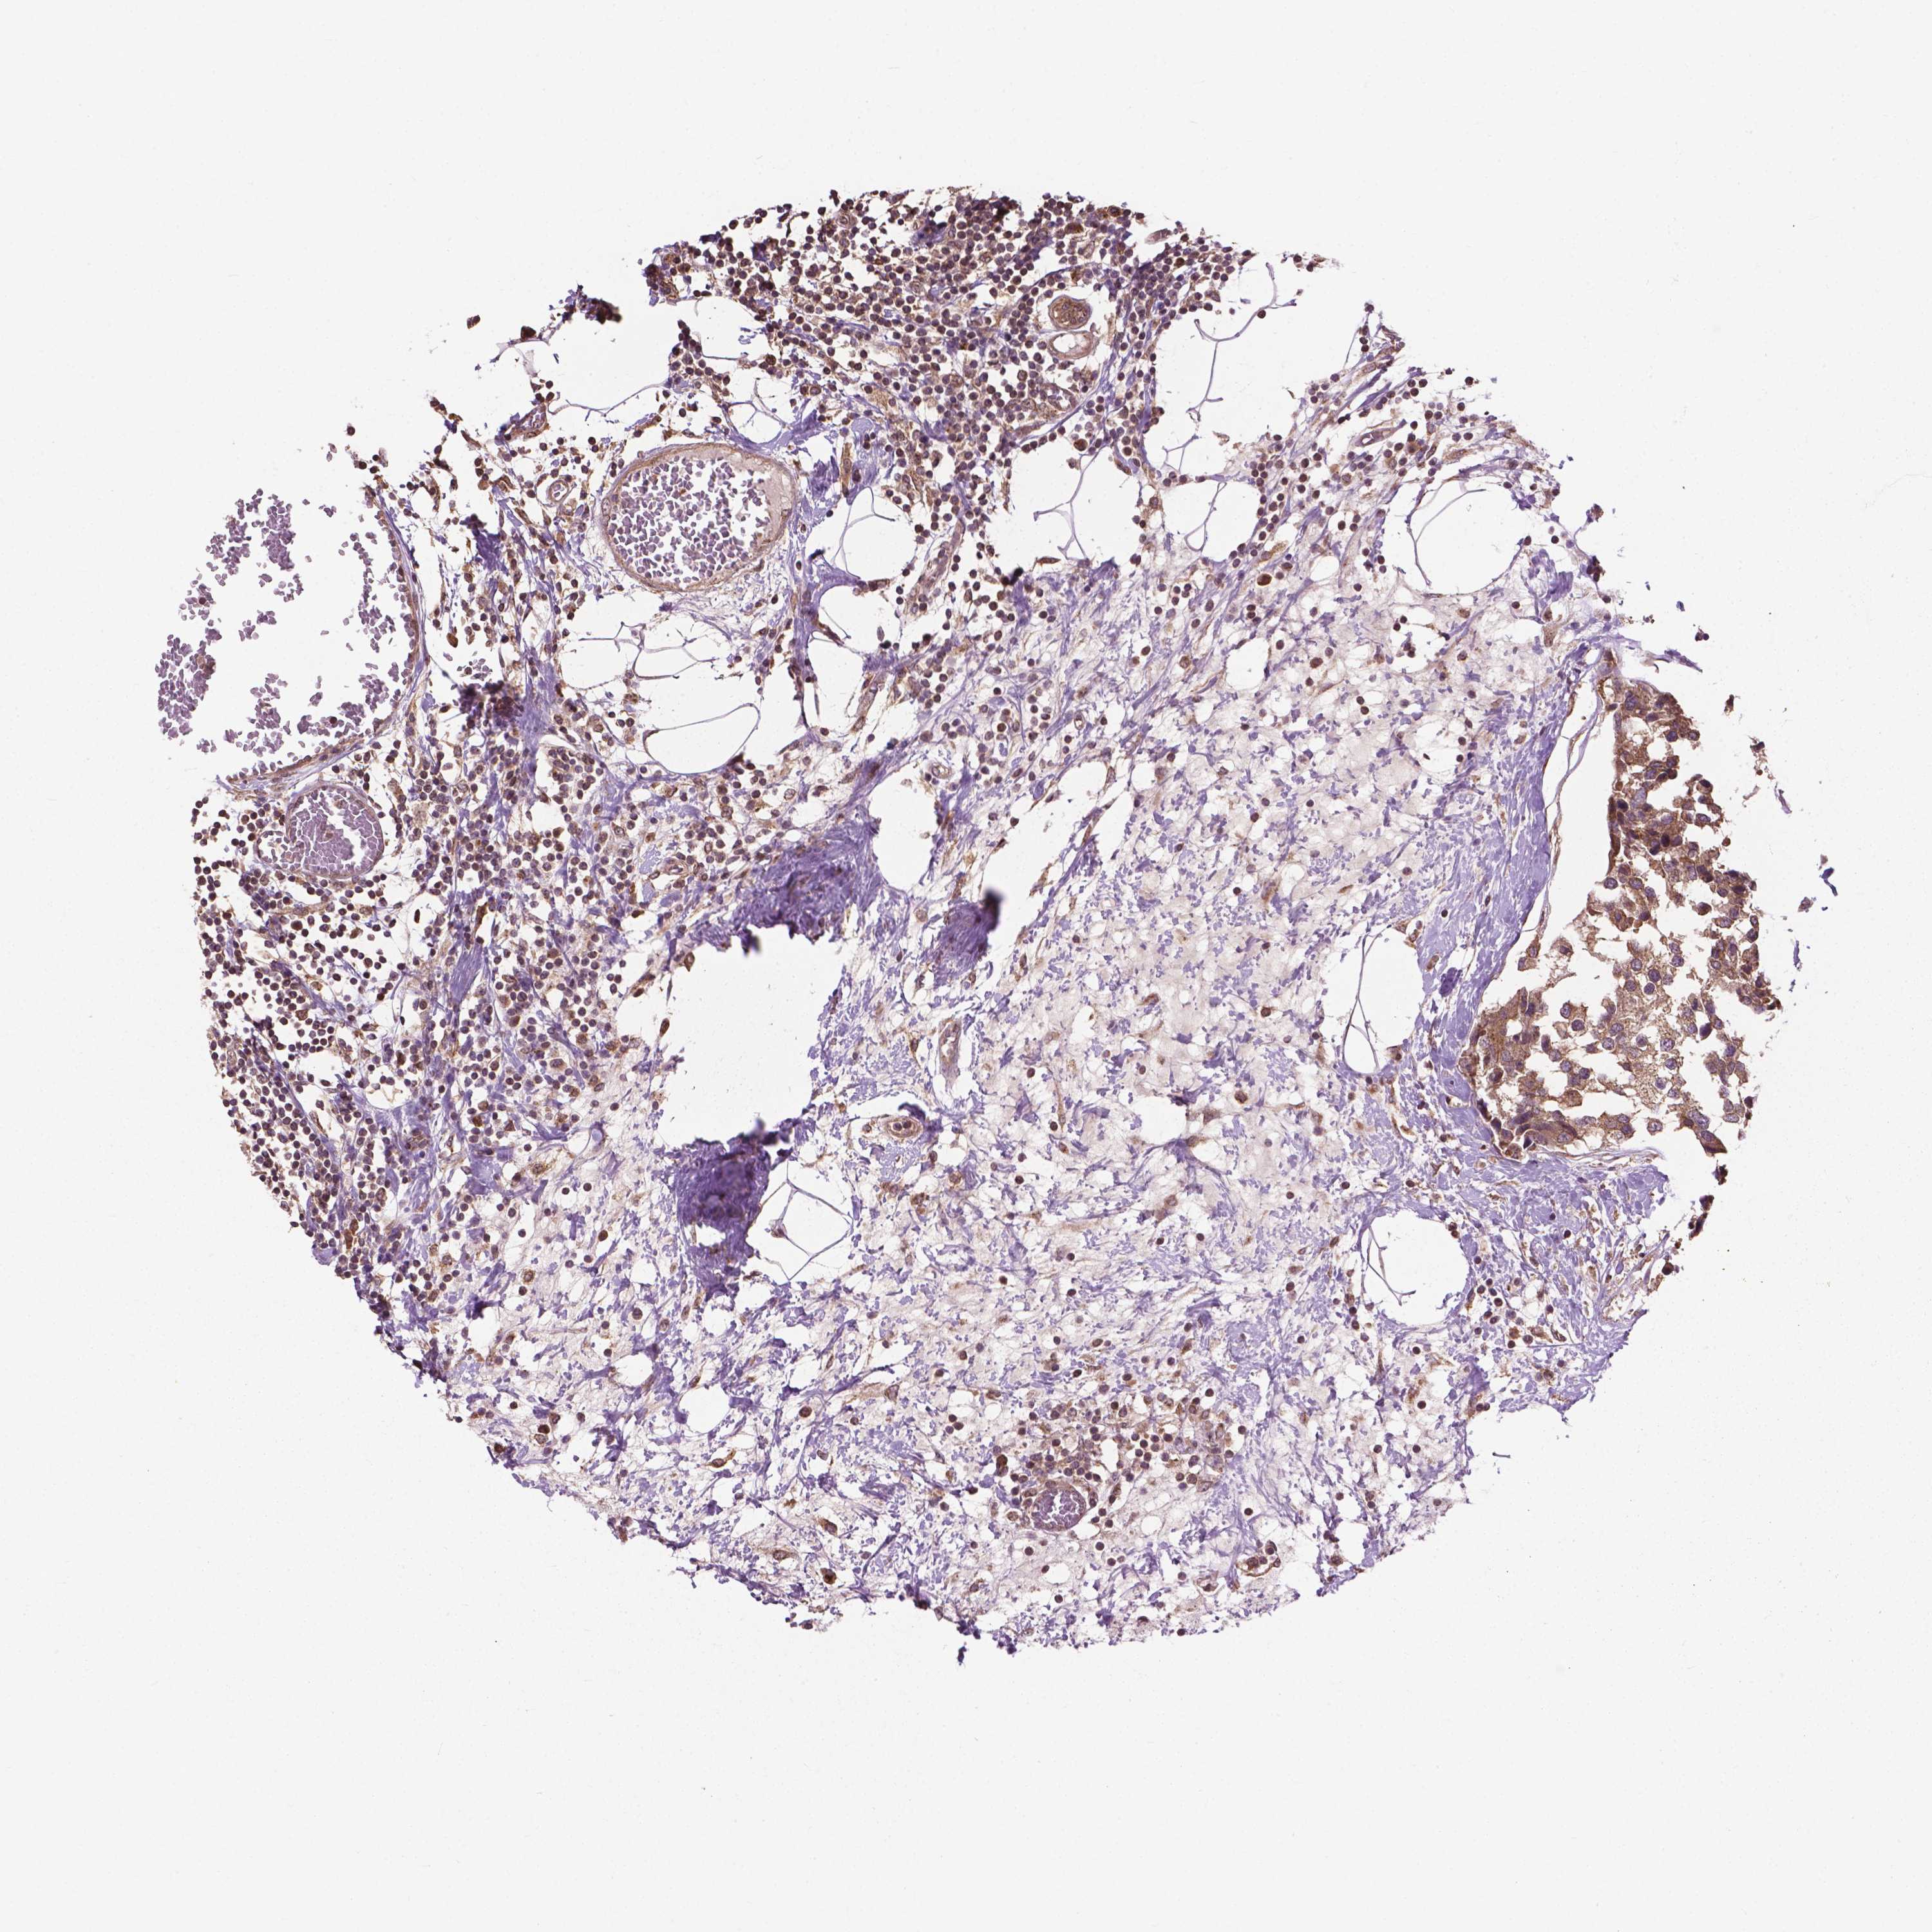

CANCER BREAST CANCER Show tissue menu

BRCA TCGA BRCA VALIDATION PROTEIN EXPRESSION

ANTIBODIES

AND

VALIDATION